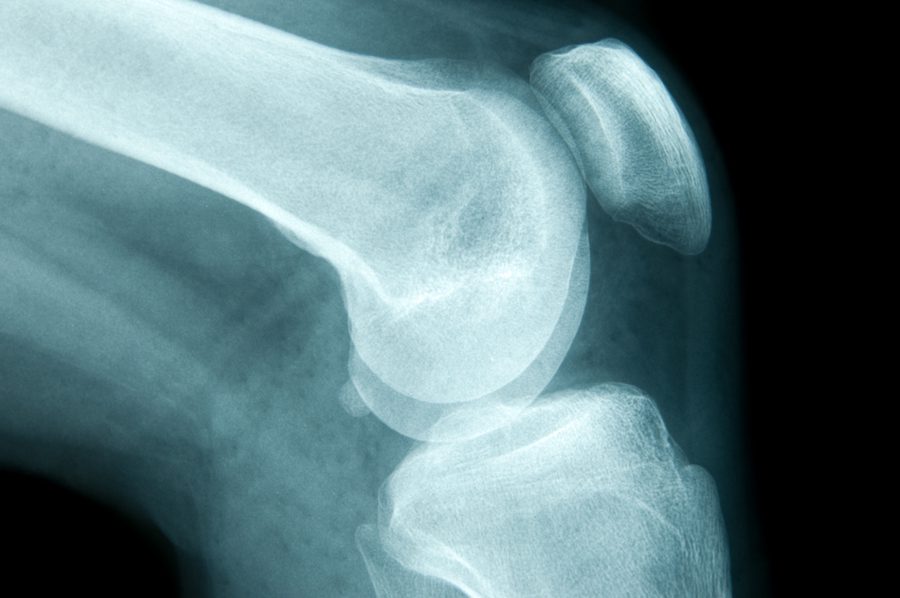

Guide to Severe Knee Arthritis (Osteoarthritis) Spring Loaded Technology

Osteoarthritis Knee ( OA Knee ). Film Xray Both Knee ( Front View Knee Cartilage Loose A meniscus tear is a common knee injury caused by sports or wear and tear. A loose body in the knee is a small fragment of cartilage or bone that is suspended in the knee fluid, otherwise known as “synovium”. A traumatic injury often causes a broken bone, but a loss of. A loose body is essentially a fragment of. Knee Cartilage Loose.